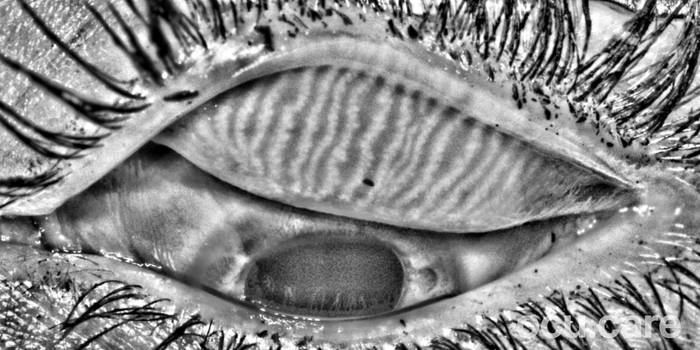

MEA – Dry Eye Examination Made Simple

Our focus is on bringing objective, image-based assessment of the ocular surface into routine workflows—whether in primary care optometry, contact lens clinics, pre-operative cataract pathways, oculoplastic and refractive surgery clinics, glaucoma clinics, or dedicated dry eye clinics—helping clinicians “see earlier” and intervene sooner.